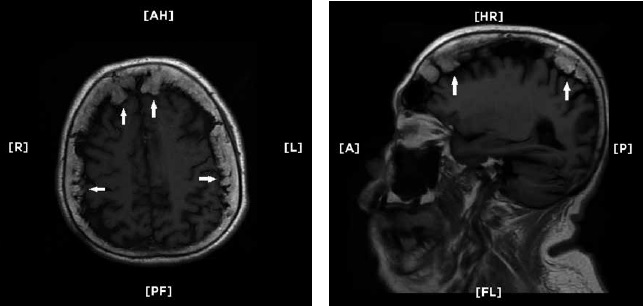

A su ingreso al área de Admisión Continua se documentó una cifra de tensión arterial de 190/100 mm Hg. En la exploración física se encontró con alteración en las funciones mentales superiores, así como hemiparesia derecha. Se realizó una tomografía computada simple de cráneo donde se reportó con parénquima cerebral homogéneo y normal, atrofia cortical y ventriculomegalia compensatoria pero con múltiples nódulos en la superficie interna del hueso frontal y de ambos parietales (figura 1). La resonancia magnética de cráneo documentó un infarto lacunar talámico izquierdo reciente y corroboró la presencia de la enostosis craneal (figura 2). El electroencefalograma realizado resulto normal para la edad de la paciente, sin actividad epileptiforme ni datos compatibles con encefalopatía.

Imágenes de resonancia magnética de cráneo en modo T-1, corte axial (izquierda) y parasagital (derecha). Se observa sobrecrecimiento óseo nodular irregular que involucra a hueso frontal y ambos parietales (flecas) así como atrofia cortical